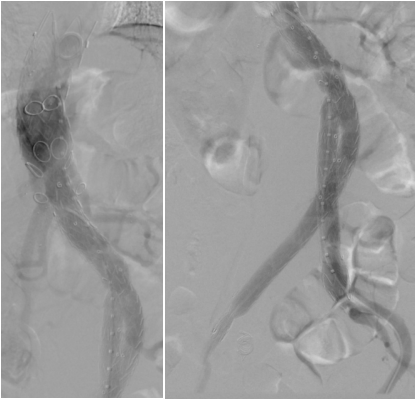

术中支架系统植入后造影

术后三天复查CTA影像,支架位置良好、各分支通畅、瘤腔封闭良好